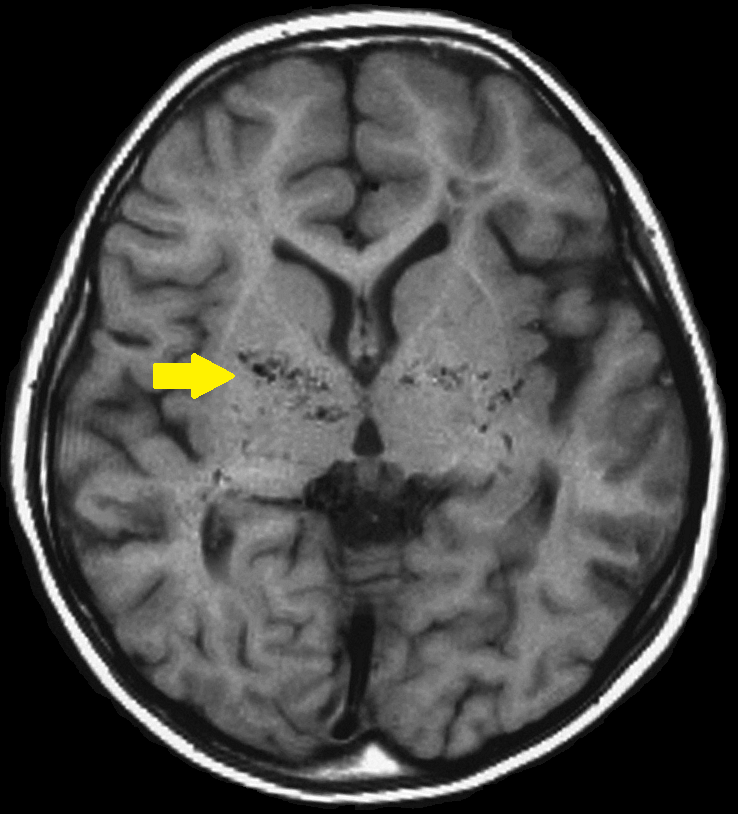

모야모야병은 뇌혈관 중 하나인 내경동맥이 막혀 혈류가 제한되는 질병입니다.

이 질병은 뇌혈관 촬영을 통해 확인되며, 때때로 뇌혈관에서 "담배 연기"처럼 보이는 혈류 모양 때문에 모야모야라는 용어로 불리게 되었습니다.

측부혈행이 생겨 막힌 혈류를 보충하려 하지만, 이는 출혈이나 혈전증과 같은 문제를 유발할 수 있습니다.